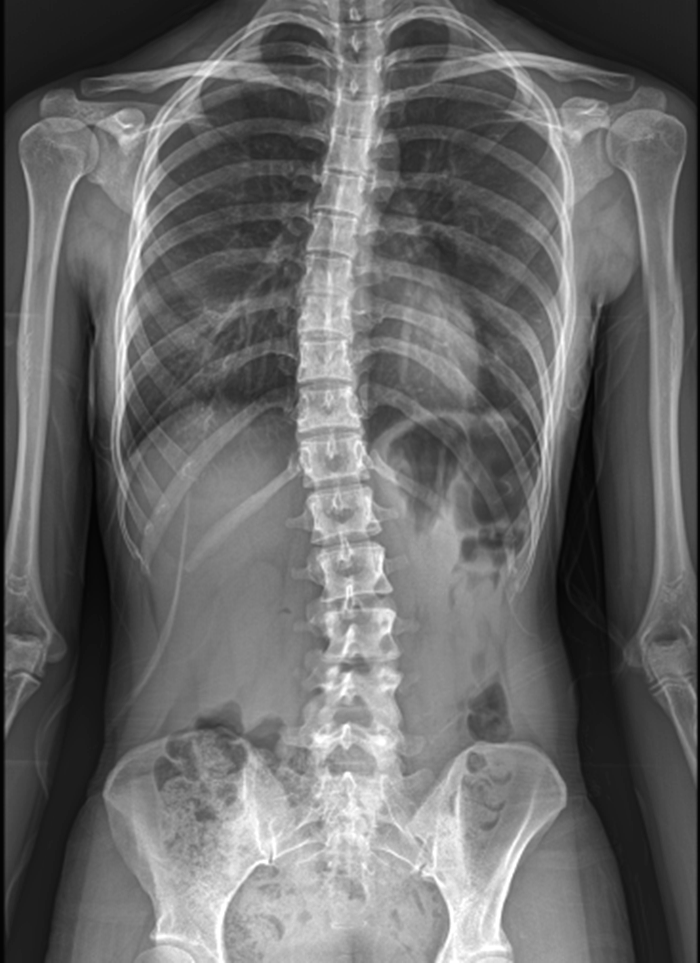

한 사례를 살펴보면 엑스레이상 척추측만증이 보이며 모아레에서도 등고선 차이로 체형이 틀어졌음을 확인할 수 있습니다.

엑스레이상에서는 척추가 어떻게 휘었는지 확인이 가능하고 골반이 어떻게 틀어졌는지 확인이 가능하지만 경근무늬측정검사를 확인해서는 정확하게 알기는 어렵지요.

하지만 반대로 엑스레이만 봤을 대는 근육이 어떻게 좌우가 다르게 긴장했는지 확인이 어렵습니다.

그렇기 때문에 이 두가지를 함께 확인하는 것이 효율적입니다.